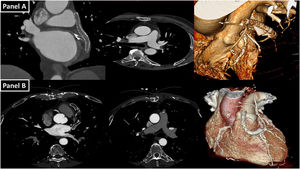

Panel A: Coronal and axial computed tomography (CT) image and three-dimensional (3D) reconstruction showing complete thrombosis of the circumflex artery, fully contained within the VEST device. Panel B: Axial CT image and 3D reconstruction showing severe stenosis at the origin of a radial artery graft to the second obtuse marginal branch and at the origin of an SVG to the right coronary artery. Additionally, there is a marked thinning and a significant reduction in the graft's lumen within two VEST-supported sequential bypasses.

The first case shows complete thrombosis of an SVG entirely contained within the VEST device, documented one year after surgery (Figure 1, Panel A). The second case demonstrates severe stenosis at the origin of a radial artery graft to the second obtuse marginal branch and at the origin of an SVG to the right coronary artery. Additionally, there is marked thinning and a significant reduction in the graft's lumen within two VEST-supported sequential bypasses (Figure 1, Panel B).